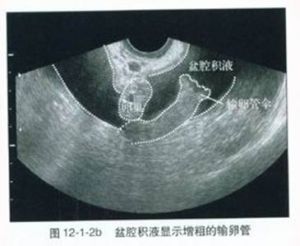

腹腔鏡有助於盆腔包塊的診斷。盆腔B型超聲檢查見子宮一側或雙側發現腫塊,其輪廓不清楚,周圍有濃密回聲,腫塊內無回聲,腫塊與子宮有界限。